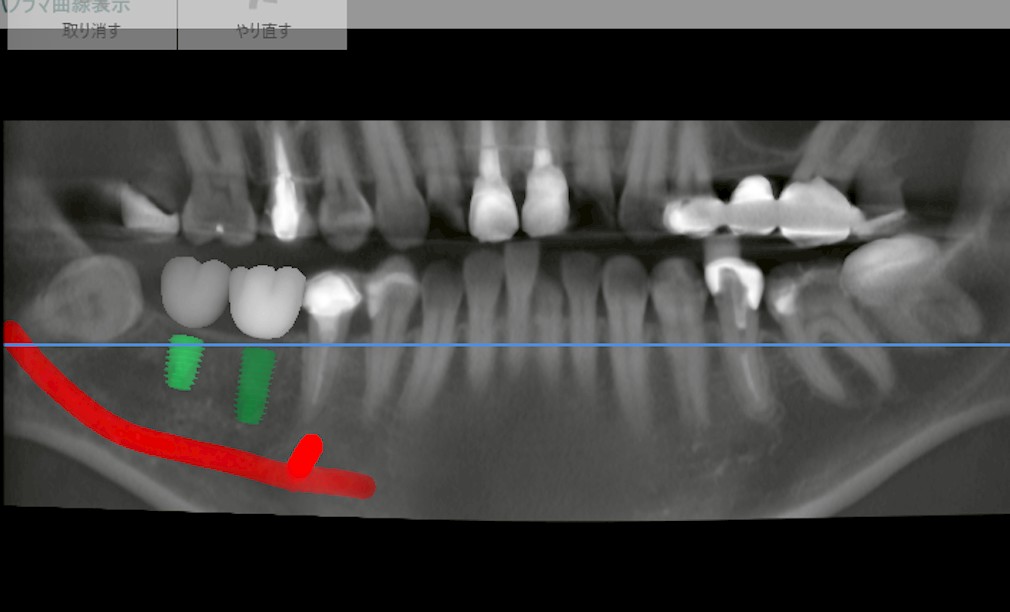

本日は、右下に2本のインプラント埋入を希望されて来院された患者様のケースをご紹介します。

診査の結果、欠損部自体に大きな問題はありませんでした。

しかし、欠損期間が長かったために頬側の骨が吸収し、やや狭窄(幅が細く)した状態となっていました。

このようなケースでは、単にCT画像やレントゲンだけを見てプランを立てるのではなく、実際の患者さんの状態(骨の厚み・開口量・筋の動きなど)を考慮することが非常に重要になります。

今回の症例で特に注目すべき点は、「開口量」です。

インプラントは骨に対して垂直に埋入することが理想ですが、口が十分に開かない場合、そもそも器具を正しい角度で挿入できません。

特に一番奥の歯(第二大臼歯部など)では、開口量が小さいだけで手技的に非常に難しくなるのです。

また、サージカルガイドを使用する場合、装着によってさらに厚みが増すため、器具(バー)が入らなくなるというリスクもあります。

* 長いインプラントを選ぶと物理的に入らない可能性がある

* ガイドを使用するとさらにアクセスが制限される

といった理由から、やや短いインプラントを選択し、ガイドを用いずに慎重に埋入を行う方針としました。